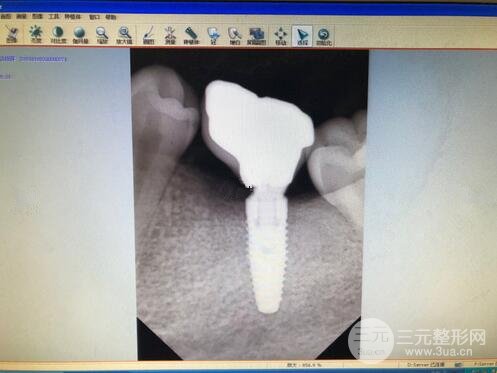

種植前后拍片、種植手術(shù)

所以等了4個(gè)月,然后拍片,看牙骨是否長滿

然后準(zhǔn)備種植,打*藥,整個(gè)過程40多分鐘

醫(yī)生說如果牙骨不夠的話

種植后可能會(huì)松動(dòng),就需要種植骨f,大概一千塊錢

吃稀飯度日一周,就等種植釘長好,大概三個(gè)月